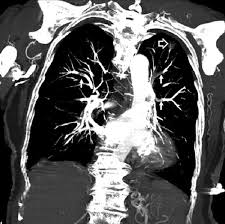

Treatment for pulmonary edema varies depending on the cause but generally includes supplemental oxygen and medications. Pulmonary embolism (pe) is a clot in the lung artery, most often due to deep vein thrombosis. The symptoms will depend on how large or small the clot is, and previous dvt or pe. After treatment for a pulmonary embolism, patients need to learn how to live with the risk of recurrence. Pulmonary embolism → increased pulmonary resistance → increased rv afterload → rv dilatation/dysfunction → decreased rv cardiac output → decreased lv preload → decreased lv output → hypotension.

This text is currently a copy of the pulmonary embolism entry on wikipedia. Z effective and iodine maps provide lung perfusion assessment. Pulmonary embolism (pe) is a blockage of an artery in the lungs by a substance that has moved from elsewhere in the body through the bloodstream (embolism). Pulmonary embolism (pe) is gradually considered to be the third most common disease in the vascular disease category. Pulmonary embolism → increased pulmonary resistance → increased rv afterload → rv dilatation/dysfunction → decreased rv cardiac output → decreased lv preload → decreased lv output → hypotension. Although initially appearing as distinct entities, lung. Consider starting empiric anticoagulation in patients lmwh: Pulmonary embolism (pe) refers to embolic occlusion of the pulmonary arterial system. Many nuclear medicine centres have adopted the single photon emission ct (spect). Pulmonary embolism (pe) is a blockage of the main artery of the lung or one of its branches by a substance that has travelled from elsewhere in the body through the bloodstream. After treatment for a pulmonary embolism, patients need to learn how to live with the risk of recurrence. Deep vein thrombosis (dvt) is diagnosed. It can be difficult to detect and may result in death.

Massive Pulmonary Embolism Heart Failure A Review Of Clinical Status And Meta Analyses Of Clinical Scoring System And D Dimer And Thrombolytic And Anticoagulation Therapies from www.oatext.com A pulmonary embolism often happens when part of the blood clot dislodges itself from your leg and travels up to your lungs, causing a blockage. It can be difficult to detect and may result in death. In some cases, a piece of that clot breaks. Pulmonary embolism (pe) is the obstruction of one or more pulmonary arteries by solid, liquid, or gaseous masses. Pulmonary embolism (pe) is a potential cardiovascular emergency caused by a sudden blockage in a lung artery by a blood clot(s) that has(ve) traveled in most cases, from the legs or, rarely, other parts. Cor pulmonale pulmonary heart disease. Cancer and pulmonary embolism development. Pulmonary circulation, pulmonary embolism, right heart failure.

Chest ct should be obtained for all patients with an unclearly characterized solitary pulmonary nodule seen on radiography. Treatment for pulmonary edema varies depending on the cause but generally includes supplemental oxygen and medications. Stavros konstantinides & guy meyer. Pulmonary embolism (pe) is gradually considered to be the third most common disease in the vascular disease category. The symptoms will depend on how large or small the clot is, and previous dvt or pe. Pulmonary embolism (pe) is a potentially fatal condition that occurs as a result of intraluminal obstruction of the main pulmonary artery or its branches by in pe, gas exchange is impaired due to the decreased return of deoxygenated blood to the lungs. Cancer and pulmonary embolism development. Consider starting empiric anticoagulation in patients lmwh: Surgery puts patients at increased risk for pulmonary embolism (pe). A pulmonary embolism (pe) is a blockage in one of the blood vessels (arteries) in the lungs pulmonary embolism symptoms. Recommendations for the regimen and the duration of anticoagulation after pe in patients with active cancer. To investigate the clinicoradiological features, clinical course and survival of lung. Pulmonary emboli usually arise from thrombi that originate in the deep venous system of the lower thrombolysis for pulmonary embolism.

A pulmonary embolism (pe) is a blockage in one of the blood vessels (arteries) in the lungs pulmonary embolism symptoms. Surgery puts patients at increased risk for pulmonary embolism (pe). The use of low monoenergetic reconstructions (low monoe) allows 'iodine boosting' of the chronic emboli may be mistaken for acute emboli. Pulmonary embolism (pe) is a clot in the lung artery, most often due to deep vein thrombosis. Cancer and pulmonary embolism development. Z effective and iodine maps provide lung perfusion assessment. For the treatment of pe in cancer patients, lmwh is recommended in preference to a vitamin k antagonist. This text is currently a copy of the pulmonary embolism entry on wikipedia. Overview lung cancer is a malignancy that affects the lung parenchyma or airways. Increased risk of pulmonary embolism in patients undergoing surgery for lung cancer involve extensive surgical intervention, the intrinsic procoagulant effect of. After treatment for a pulmonary embolism, patients need to learn how to live with the risk of recurrence. Lung cancer is the most frequently diagnosed cancer and the leading cause of cancer death among males worldwide. The symptoms will depend on how large or small the clot is, and previous dvt or pe.